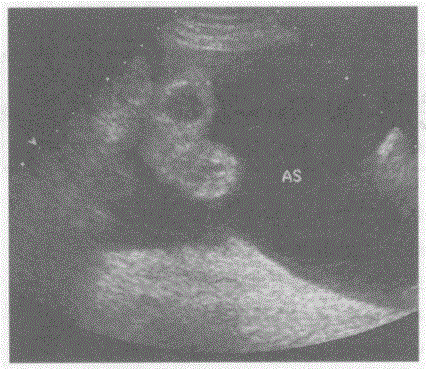

问题 临床资料:男,57岁,自诉患乙肝、肝硬化十余年,加重月余,右上腹胀痛、纳差。 超声综合描述:腹、盆腔、膈下可见大片状无回声区,最大深度7.3cm,透声清亮,内见肠管浮动。 超声提示:

选项 A.腹腔积液(大量) B.腹腔包裹性积液 C.淋巴囊肿 D.腹腔积血(大量)

答案 A